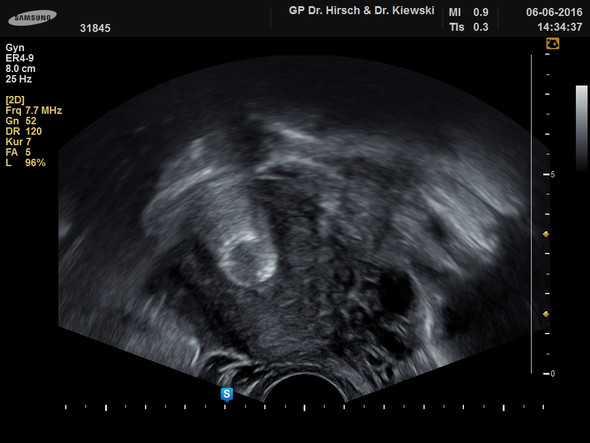

Erkunde Nancy Schreibers Pinnwand „Geometrische schablone“ auf Weitere Ideen zu Geometrische schablone, Geometrisch, Schmuck. Mit dem Silberring an der Jaydess®Spirale wurde eine deutliche Verbesserung für die Abläufe bei den regelmäßigen Lagekontrollen geschaffen Abb 7 Der Silberring am oberen Ende der Jaydess®Spirale ist in diesem Bild direkt getroffen und bildet ein markantes Kennzeichen der Spirale. Spirale verrutscht Hallo, meine Spirale (Goldluna) ist nach 2,5 Jahren verrutscht und liegt nicht mehr mittig in der Gebärmutter Meine Frauenärztin meinte, dass dadurch natürlich die Verhütung nicht mehr sicher ist Nun muss ich mir überlegen, ob ich mir eine neue Spirale legen lasse Ich war.